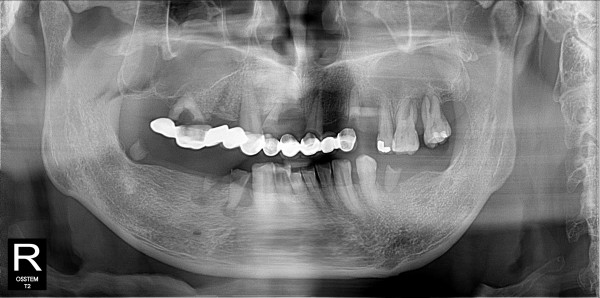

구치부 임플란트